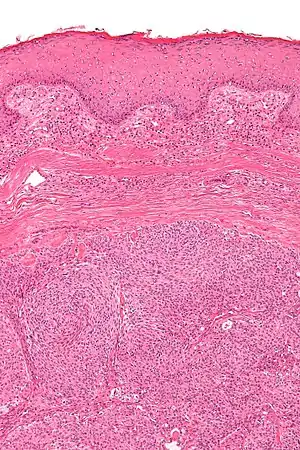

| Micrograph showing an acrospiroma. H&E stain. | |

Discussion of sweat gland tumors can be difficult and confusing due to the complex classification and redundant terminology used to describe the same tumors. For example, acrospiroma and hidradenoma are synonymous, and sometimes the term acrospiroma is used to generally describe benign sweat gland tumors. In addition, a single lesion may contain a mixture of cell-types.[2] There has also been a change in understanding about how tumors that were previously believed to strictly derive from specific sweat gland types may, in fact, derive from both eccrine or apocrine glands.[5][6]